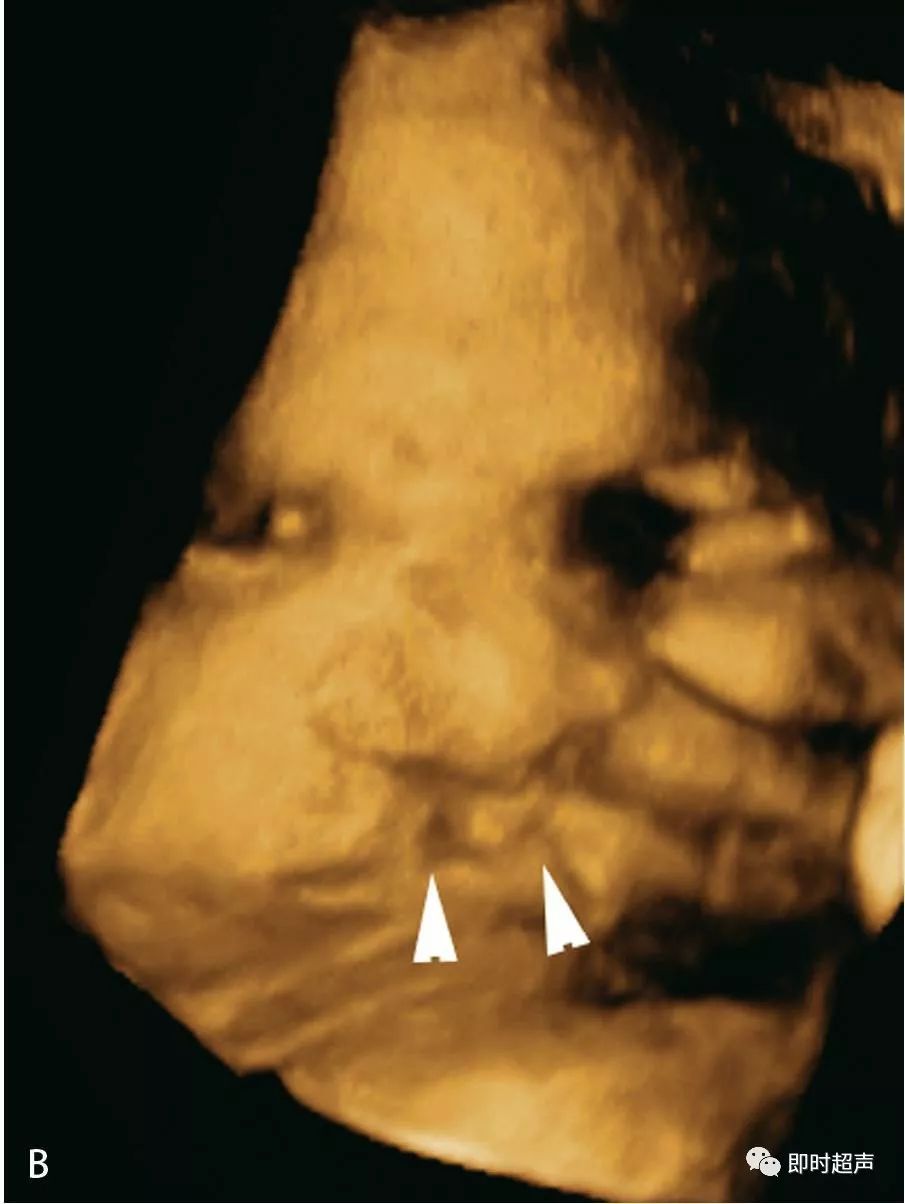

1.2三维超声显示单侧唇裂.

(c,d)三维图像示正中唇裂(箭头)延伸至鼻.

唇颚裂三维图